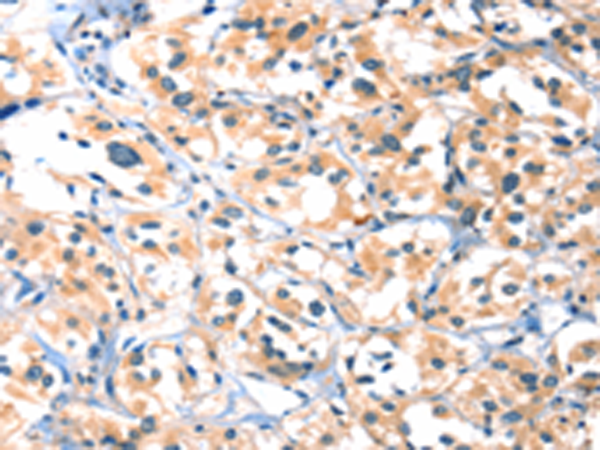

分类: 科研抗体货号: P11573别名: HYDM; PAN7; NALP7; NOD12; PYPAF3; CLR19.4应用: IHC反应种属: Human